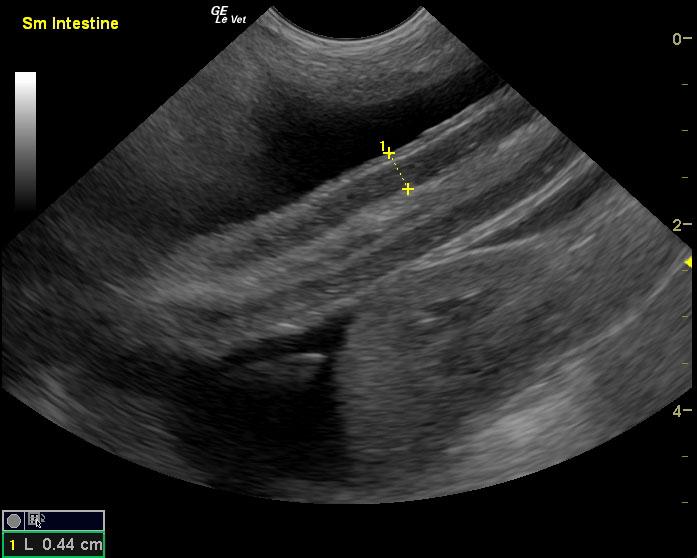

Protein losing enteropathy.

Lymphangectasia type presentation with secondary ascites.

If the ascites is transudate based on abdominocentesis this would be most consistent with protein losing enteropathy and secondary albumin loss, but given that the bloodwork was taken 4 days prior to the sonogram my concern is that the albumin is likely lower than 1.7 at this point. Anything less than 1.5 would justify poor oncotic pressure and free fluid formation. Urinalysis and assessment for concurrent protein losing nephropathy would be recommended. Liver function may also be compromised adding to the albumin loss issue. Plasma transfusion, broad spectrum deworming, calcium supplementation, Purina HA or Royal Canin HP diet, Metronidazole and Prednisone therapy would all be indicated. However, corn oil testing and endoscopy would be ideal for a definitive diagnosis as well as mucosal, gastric and duodenal biopsies.